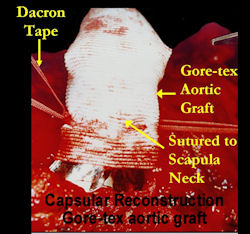

Examples of radical limb sparing surgeries for osteosarcomas in various anatomic locations (distal femur, proximal tibia, proximal humerus, scapula)

In each case, the tumor and bone from which it arose were resected. This required meticulous dissection, mobilization and preservation of adjacent pertinent neurovascular structures. In each case presented here, the defect was reconstructed with a special modular segmental tumor prosthesis. This also replaces the adjacent joint in many instances.

Proximal Humerus: Radical Limb Sparing Extra-Articular Resection and Prosethetic Reconstruction